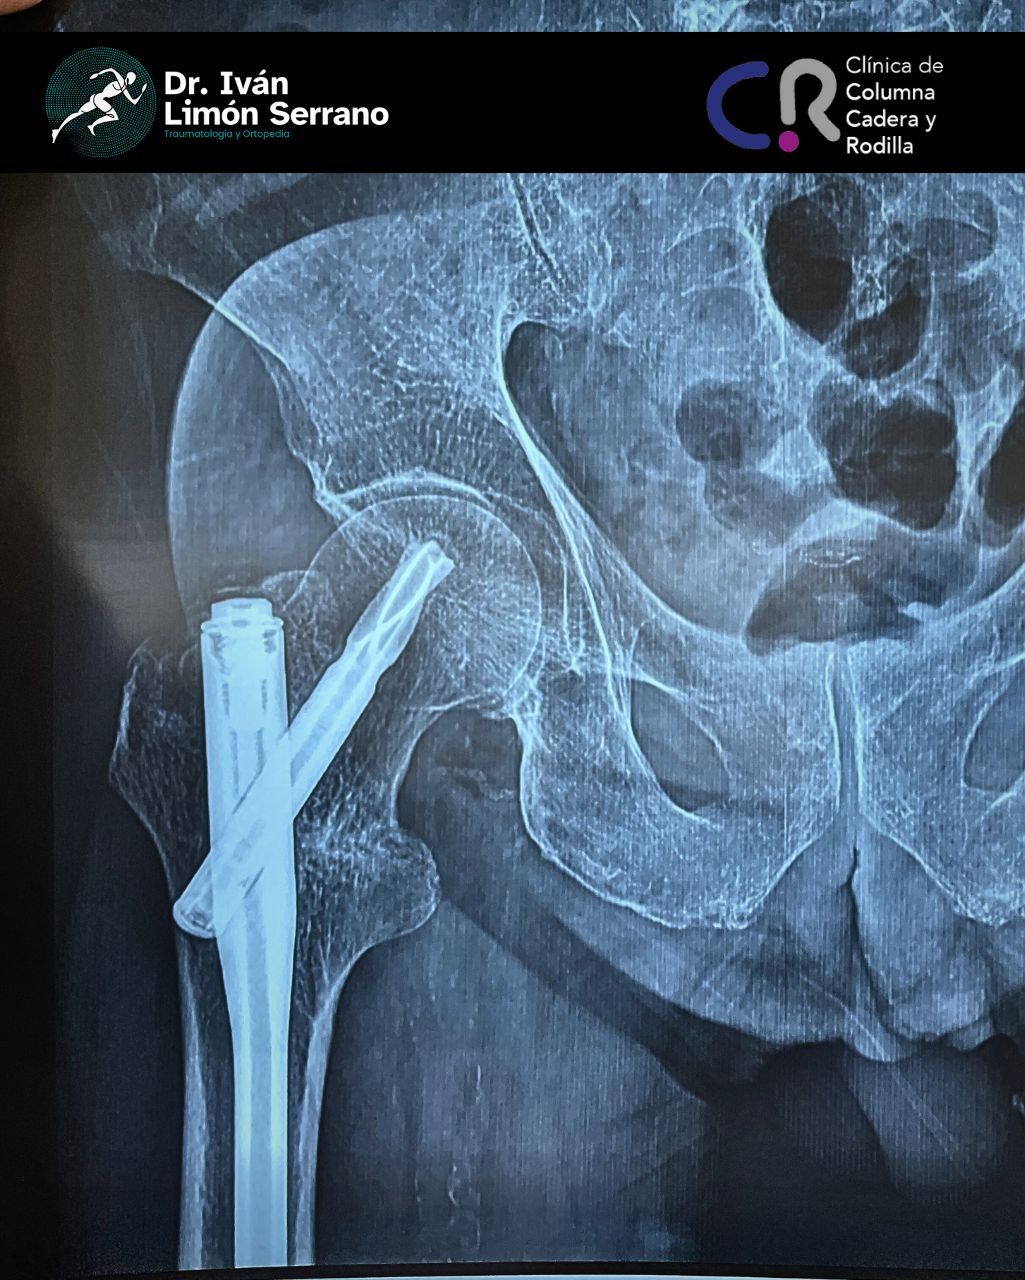

• Prótesis de cadera

• Cirugía cadera

• Artroscopia de cadera

Es una enfermedad articular caracterizada por la por degeneración, perdida del cartílago y alteración del hueso subcondral asociado a cambios en tejidos blandos. Se caracteriza por dolor articular, limitación funcional, crepitación y grados variables de inflamación. Factores de riego como sobrepeso, obesidad, debilidad muscular, actividad física pesada traumatismos, edad avanzada, sexo femenino, factores genéticos, trastornos metabólicos y congénito. Actualmente existen tratamientos desde lo no farmacológico control de peso hasta el tratamiento quirúrgico como lo es el reemplazo articular mediante la colocación de prótesis total.